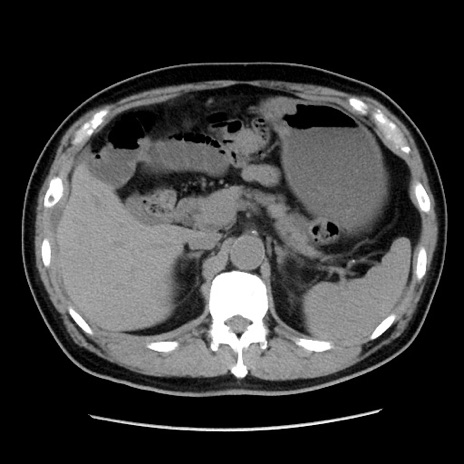

症例16(横断像)

【症例】 70歳代男性

【主訴】 腹痛、嘔吐

【現病歴】 約1ヶ月前より間欠的に腹痛と嘔吐あり、当院消化器内科を受診したところCTで多発する肝臓のLDAを指摘され、精査中であった。以降は消化器症状は安定していたが、2日前より嘔気と腹痛があり、同日より排便・排ガスが消失した。改善認めず、 本日、救急外来を受診した。

【既往歴】 大腸ポリープ切除後。

【身体所見】意識清明・会話良好、BT 36.3℃、BP 127/80mmHg、 P 80bpm、腹部:膨満あり、平坦・軟、上腹部正中および下腹部正中に圧痛あり、反跳痛なし、筋性防御なし。

【データ】WBC 7200、CRP 0.77